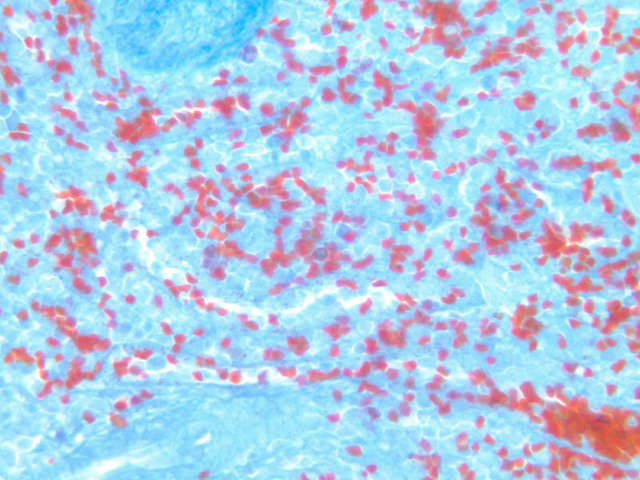

Sections through the spleen (slides A-36, aniline blue [2.5x, 10x, 20x-labeled, 40x] [2.5x, 10x-labeled, 20x-labeled, 40x]; A-37, retic [2.5x, 10x, 20x-labeled, 40x]; A- 37, H&E [2.5x-labeled, 10x, 20x, 40x]; A-38, H&E [10x, 20x, 40x]; A-39, H&E [2.5x, 10x, 20x, 40x]) show a thick investing capsule composed of collagenous tissue and smooth muscle, typically covered with mesothelium. In slide A-36 muscle and collagen are brightly stained. The capsule and mesothelium completely surround the organ and the fibrous portion enters the splenic substance at the hilus around the splenic arteries and veins forming trabeculae of fibromuscular tissue within the splenic substance. This fibromuscular tissue enables the spleen to expel blood by contracting. Identify trabeculae as fibrous partitions in the section and look for blood vessels within them.

Where the trabecular arteries pass into the splenic pulp, they become invested by a sleeve of lymphoid tissue. This lymphatic tissue collectively forms the white pulp of the spleen (A-36 [2.5x, 10x, 20x, 40x]). It also is referred to as the periarterial lymphatic sheath or PALS. On an H&E stained section (A-38 [2.5x, 10x, 20x, 40x] [2.5x, 10x, 20x, 40x]) the white pulp will appear as basophilic clumps of lymphoid cells. The arteries of the white pulp are called central arteries, although they may be displaced to one side of the lymphoid sleeve by the presence of a nodule. The majority of cells forming the PALS are T lymphocytes. In places the covering of lymphatic tissue is enlarged due to the presence of lymphoid nodules (splenic or Malphighian corpuscles) which are comprised predominantly of B lymphocytes.

The remainder of the cellular mass in the spleen is red pulp (A-38 [10x, 20x, 40x]), made up of red and white cells of the blood enmeshed in the reticular tissue of splenic cords and present in the splenic sinuses. After passing through the PALS, the trabecular arteries branch to form smaller arterial vessels known as penicillar arterioles which narrow, forming arterial capillaries that empty into the cords of the red pulp (open circulation) or into the venous sinuses (closed circulation). In the splenic sinuses the cells of the blood are exposed to red pulp macrophages. The splenic sinuses eventually become confluent to form veins that enter the trabeculae and gradually merge meeting in the hilus to form splenic veins.

Examine the composition of the red pulp tissue. The three dimensional structure of the red pulp is analogous to Swiss cheese with the holes being the venous sinuses and the cheese being the parenchyma (i.e. splenic cords). On slide A-36 which is stained with Mallory's aniline blue locate examples of the splenic sinuses ([2.5x, 10x, 20x, 40x-labeled] [10x, 20x, 40x]). The walls of the splenic sinuses consist of adjoining specialized endothelial cells whose nuclei in many cases stand out from the wall in a bead-like fashion. The basement membrane of the epithelial cells stains blue revealing the sinuses quite nicely. Usually the sinus lumen is filled with red cells and leukocytes. The skeletal framework of the cords is provided by a network of reticular fibers. As above, the reticular cells are best seen using a reticular fiber stain (slide A-37 [2.5x, 10x, 20x, 40x-labeled]). Look for the large pale nuclei of reticular cells that have darkly stained reticular fibers. Fibers run irregularly in the cords, but clearly outline the sinuses around which they are wrapped. Notice on this same slide that there is much less reticular tissue in the white pulp than the red. The splenic cords occur around the sinuses and are distinguished by the presence of disintegrating red blood cells undergoing phagocytosis.